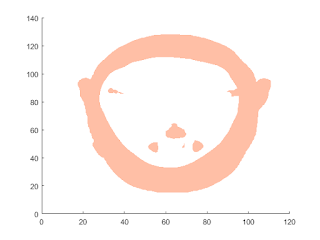

%%Isosurface to the MRI Data figure colormap(map) Ds = smooth3(D); hiso = patch(isosurface(Ds,5),... 'FaceColor',[1,.75,.65],... 'EdgeColor','none'); isonormals(Ds,hiso);

Isocaps Show Cut-Away Surface

hcap = patch(isocaps(D,5),... 'FaceColor','interp',... 'EdgeColor','none');

Defining the View

%Define the view and set the aspect ratio (view, axis, daspect). view(75,30) axis tight daspect([1,1,.4]) lightangle(75,30);

lighting gouraud

hcap.AmbientStrength = 0.5;

hiso.SpecularColorReflectance = 0;

hiso.SpecularExponent = 60;